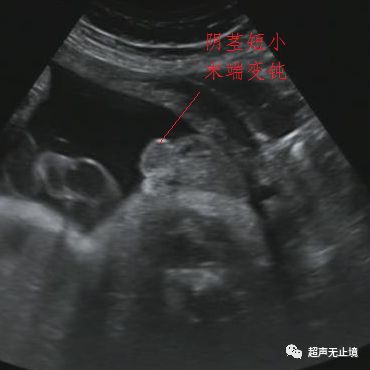

阴茎末端变钝

阴茎短*r>